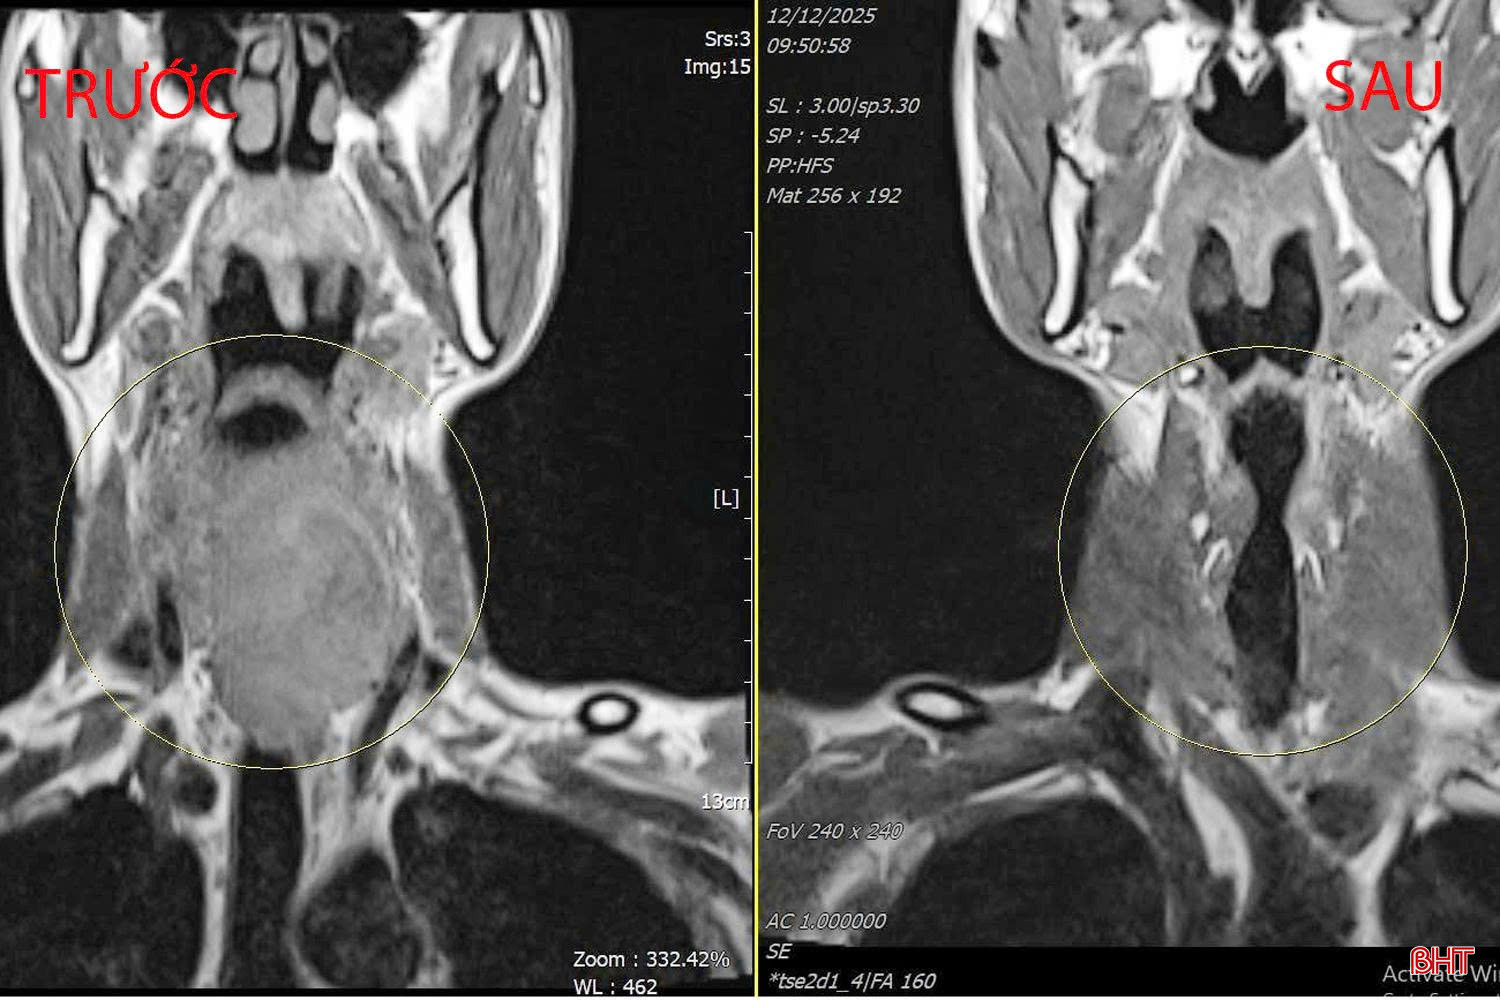

Điển hình như trường hợp bệnh nhân N.V.C (43 tuổi, xã Cẩm Xuyên) khi biết mình bị mắc ung thư hạ họng và thực quản đã vô cùng lo lắng. Ngay sau đó, bệnh nhân được chuyển đến BVĐK tỉnh để điều trị. Trên cơ sở tình trạng của bệnh nhân, các bác sĩ Khoa Ung bướu - Y học hạt nhân đã tiến hành lên phác đồ điều trị, trong đó tiến hành phẫu thuật mở thông dạ dày và triển khai các đợt xạ trị. Qua 35 đợt xạ trị cho thấy, bệnh nhân đáp ứng tốt, các tổn thương đích ở 2 khối u biến mất hoàn toàn.

bqbht_br_xa-tri-7.jpg

Hình ảnh chụp phim kết quả khối u trước và sau khi triển khai xạ trị của bệnh nhân N.V.C.

Có mặt tại Khu xạ trị trong ngày đến tái khám sau xạ trị, bệnh nhân N.V.C. không giấu được xúc động: “Trước đây, nếu phải ra Hà Nội điều trị thì chi phí và sinh hoạt vô cùng tốn kém. Nay được xạ trị ngay tại tỉnh, đi lại thuận tiện, bác sĩ theo dõi sát sao. Sau các đợt xạ trị, kết quả cho thấy khối u đáp ứng hoàn toàn, tôi không phải điều trị nữa mà chỉ thăm khám và theo dõi sức khỏe. Nhận được kết quả này, gia đình tôi mừng đến rơi nước mắt.”